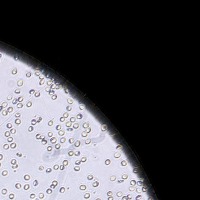

RBC Platelet v1 Computer Vision Project

Medical Diagnostic Tools: "RBC Platelet v1" can be integrated into diagnostic software systems to help physicians automatically detect and classify blood cells, aiding in faster disease diagnosis such as anemia, leukemia, or thrombocytopenia.

Biological Research: Researchers studying blood cells and diseases could use this model to automate cell identification and classification in their lab results, making for a more efficient research process.